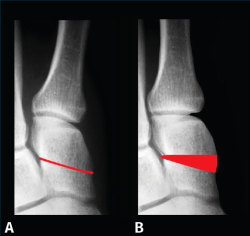

La posición del sesamoideo interno se valoró según el método propuesto por R. H. Hardy y J. C. R. Clapham(31), en una proyección radiológica dorsoplantar (Figura 4). Estos autores clasifican de 1 a 7 la posición del sesamoideo interno con relación al eje axial del primer metatarsiano, siendo 1 la posición correcta y colocándose más lateral progresivamente de la posición 1 a la 7.

Figura 4. Posición del sesamoideo tibial tomando como referencia el eje del primer metatarsiano (Hardy y Clapham).

Proponemos una clasificación práctica derivada de las propuestas por D. J. Hatch et al.(32) y de J. S. Kim y K. W. Young(33) para determinar la situación de los sesamoideos en la proyección axial, que exponemos a continuación, utilizada en este trabajo y que puede ser de ayuda para realizar el tratamiento quirúrgico más adecuado. En ella se valora “la relación espacial” del rodete con la cara articular plantar del primer metatarsiano:

• Grado 0: normal. No pronación. No desplazamiento medial del primer metatarsiano. Sesamoideos estables (Figura 5A).

• Grado I: no pronación. Desplazamiento medial del primer metatarsiano. Sesamoideos sub­luxados. Osteotomía del primer metatarsiano + cerclaje fibroso (Figura 5B).

• Grado II: pronación. Desplazamiento medial del primer metatarsiano. Los sesamoideos están en su lugar, pero en las radiografías parecen luxados. Osteotomía desrotatoria triplanar del primer metatarsiano vs. artrodesis cuneometatarsiana triplanar (Figura 5C).

• Grado III: pronación + desplazamiento medial del primer metatarsiano. Sesamoideos subluxados. Osteotomía desrotatoria triplanar de primer metatarsiano vs. artrodesis cuneometatarsiana triplanar + cerclaje fibroso (Figura 5D).

Figura 5. Clasificación de la posición de los sesamoideos en proyección coronal.